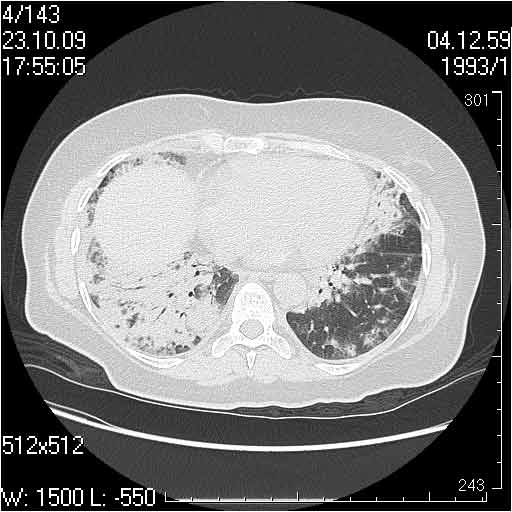

Случай №3

Женщина 51 год

Случай 3:смешанные изменения; подходят для интерстициальной пневмонии, тактика аналогична случаю 1.